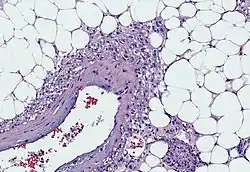

Myoid cells with clear cytoplasm spinning off of large vessels in a background of mature fat, the classic microscopic features of angiomyolipoma

An angiomyolipoma is composed of varying proportions of vascular cells, immature smooth muscle cells, and fat cells.[4] These three components respectively give rise to the components of the name: angio-, myo-, and lip-. The -oma suffix indicates a tumour.